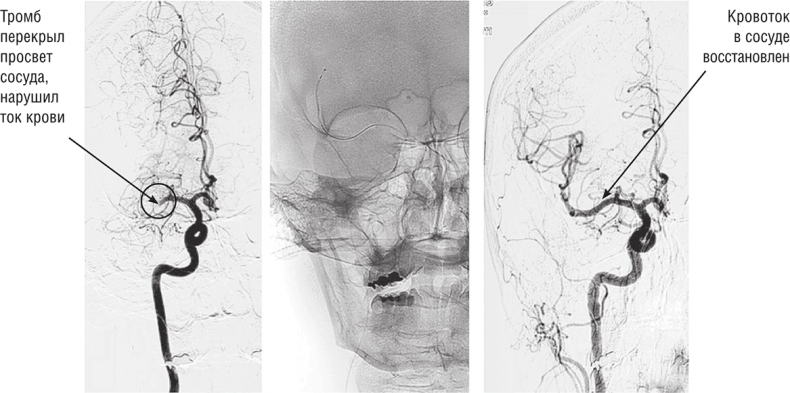

Совокупность этих факторов, безусловно, не могла устраивать врачей и требовала поиска более эффективного и безопасного метода лечения больных с острым ишемическим инсультом. Такой метод был найден! Его отличие от тромболизиса свелось к тому, что попавшие в мозговой кровоток тромбы стали убирать механически специальными инструментами, получившими название тромбоэкстракторов (от латинского слова «extractum» — извлекать, вытягивать). Это позволило избежать недостатков, свойственных тромболизису, и значительно улучшить результаты лечения пациентов. Занимаются этим методом лечения, а правильнее даже говорить — методом спасения жизни, специалисты по эндоваскулярным внутрисосудистым вмешательствам. Но обеспечивает успех лечения настоящая команда профессионалов, включая невролога, специалиста по компьютерной томографии, анестезиолога-реаниматолога.

Что же представляет собой процесс тромбоэкстракции? Не вдаваясь в совсем медицинские детали, скажем нашим читателям, что для того чтобы выполнить механическое удаление тромбов из сосудов мозга, врачу нужен специальный рентгеновский аппарат и, безусловно, соответствующие инструменты. Обычно через прокол бедренной артерии в паху пациента инструменты заводят в сосуды шеи и далее в сосуды головного мозга. Постоянно контролируя свои действия, врач подводит инструменты по сосудам внутри черепа к месту закупорки. Далее из катетера выдвигается тромбоэкстрактор — сетчатая конструкция наподобие корзинки. Происходит захват тромба, а далее его извлечение по катетерам наружу. Тромбоэкстракция может быть не только механической, но и аспирационной. В этом варианте к закрытому тромбом сосуду подводится микроотсос, который засасывает тромб внутрь катетера и выводит наружу. И тот, и другой способы удаления тромбов могут быть успешно использованы для спасения больного.

Механическая тромбоэкстракция. Основные этапы

Процесс тромбоэкстракции глазами врача